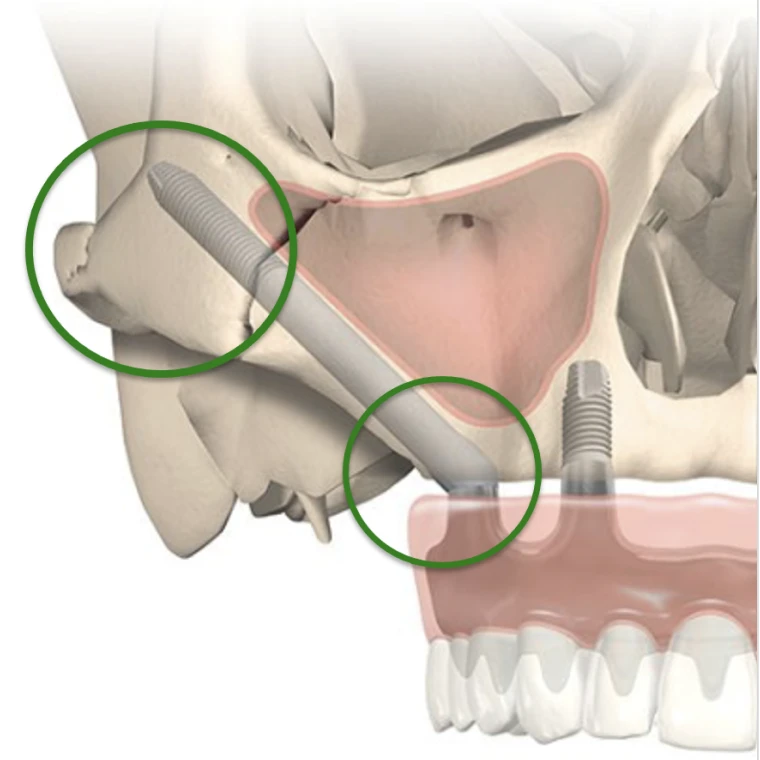

Un implant zygomatique est plus long qu’un implant en titane classique. Il mesure de 3 à 5 cm. L’os des pommettes est d’excellente qualité, il ne se résorbe pas. Son volume osseux est généralement suffisant. Chaque pommette peut recevoir un ou deux implants. La partie de l’implant visée dans l’os zygomatique est rugueuse pour une meilleure accroche et cicatrisation osseuse, l’autre partie qui traverse le sinus et la muqueuse buccale est lisse pour éviter de fixer les bactéries. Le col de l’implant est angulé à 55 degrés pour rattraper l’axe d’insertion. Un pilier (violet) est vissé dans l’implant. Son épaisseur varie de 1 à 3 mm. Il est choisie en fonction de l’épaisseur de gencive. La prothèse se visse sur le pilier.

Il existe 2 types d’implants zygomatiques, un avec un col fileté pour augmenter son accroche si le volume osseux le permet au niveau du maxillaire et un avec un col plat affleurant pour épouser les contours osseux si le maxillaire est atrophié. Si le col de l’implant est en sur-épaisseur sur le rebord osseux et non complètement entouré d’os, il y a un risque important de rétraction muqueuse et d’exposition de l’implant à l’origine d’une possible porte d’entrée bactérienne et d’une gène pour le patient.

Si l’atrophie osseuse est seulement postérieure, 2 implants zygomatiques postérieurs suffisent couplés à 2 implants antérieurs classiques, on parle de réhabilitation prothétique fixe sur 4 implants de type zygomatique hybride. Dans ce cas de figure, l’implant zygomatique est positionné en position basse de manière à garder un volume osseux disponible supérieur sur le zygoma pour placer un 2 ème implant zygomatique à distance si besoin.

Si l’atrophie osseuse concerne toute la mâchoire, 4 implants zygomatiques sont nécessaires. Ils sont placés de manière à sortir sous les incisives latérales et les 2 ème prémolaires. L’implant supérieur longe à distance du rebord orbitaire, l’implant inférieur chemine sur la plus grande longueur d’ancrage osseux quelques millimètres plus bas. Le nerf infra-orbitaire responsable de la sensibilité para-nasale et jugale doit être respecté lors de la pose implantaire au risque de trouble de la sensibilité. On parle de réhabilitation prothétique fixe sur 4 implants zygomatiques ou quad zygomatiques.

Le trajet de l’implant zygomatique dépend de l’anatomie et du volume des sinus. Il peut être à l’extérieur du sinus si le sinus est concave et de petit volume, dans le sinus si le sinus est convexe et volumineux ou à cheval. Les études cliniques actuelles ne montrent pas plus de nouvelles pathologies sinusiennes chez les patients ayant des implants zygomatiques dont le trajet est intra-sinusien.